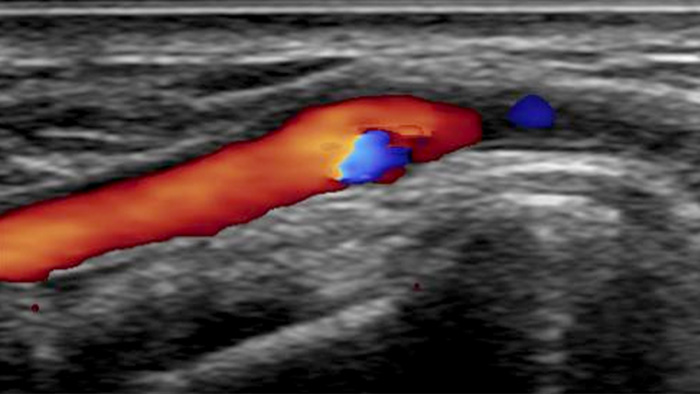

A realistic visualisation of arterial vasculature is required to effectively access the arterial system. Our integrated CX50 ultrasound system provides premium quality images of the radial artery and veins to support radial access interventions.